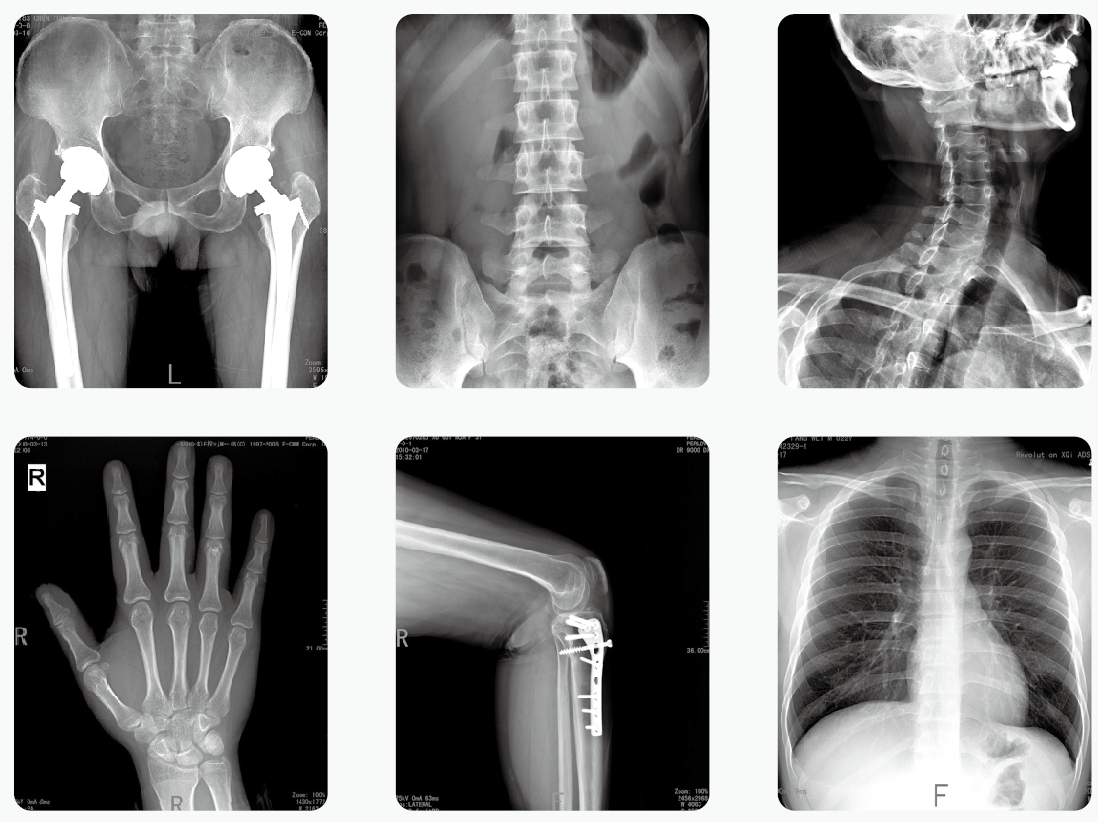

2019-nCoV肺炎的诊断都需要做X光检查来确定。2月2日,中华医学会影像技术分会传染病影像技术专业委员会专家共识协作组发布了《新型冠状病毒(2019-nCoV)感染肺炎放射检查方案与感染防控专家共识》。其中明确提出移动数字化X光机在诊疗过程中的重要性,将其作为肺炎筛查和诊断的重要工具。

移动数字化X光机、CT是新型冠状病毒感染的肺炎检查的可靠依据。如果得了新型冠状病毒肺炎,早期X线胸片影像学表现主要是双肺出现斑片影,以及间质性的改变。新型冠状病毒肺炎影像学表现多样且与其他类型肺炎存在相似影像学表现,鉴别困难。尤其和其它病毒性肺炎鉴别时,需结合流行病学、实验室检测相关资料,如核酸检测。